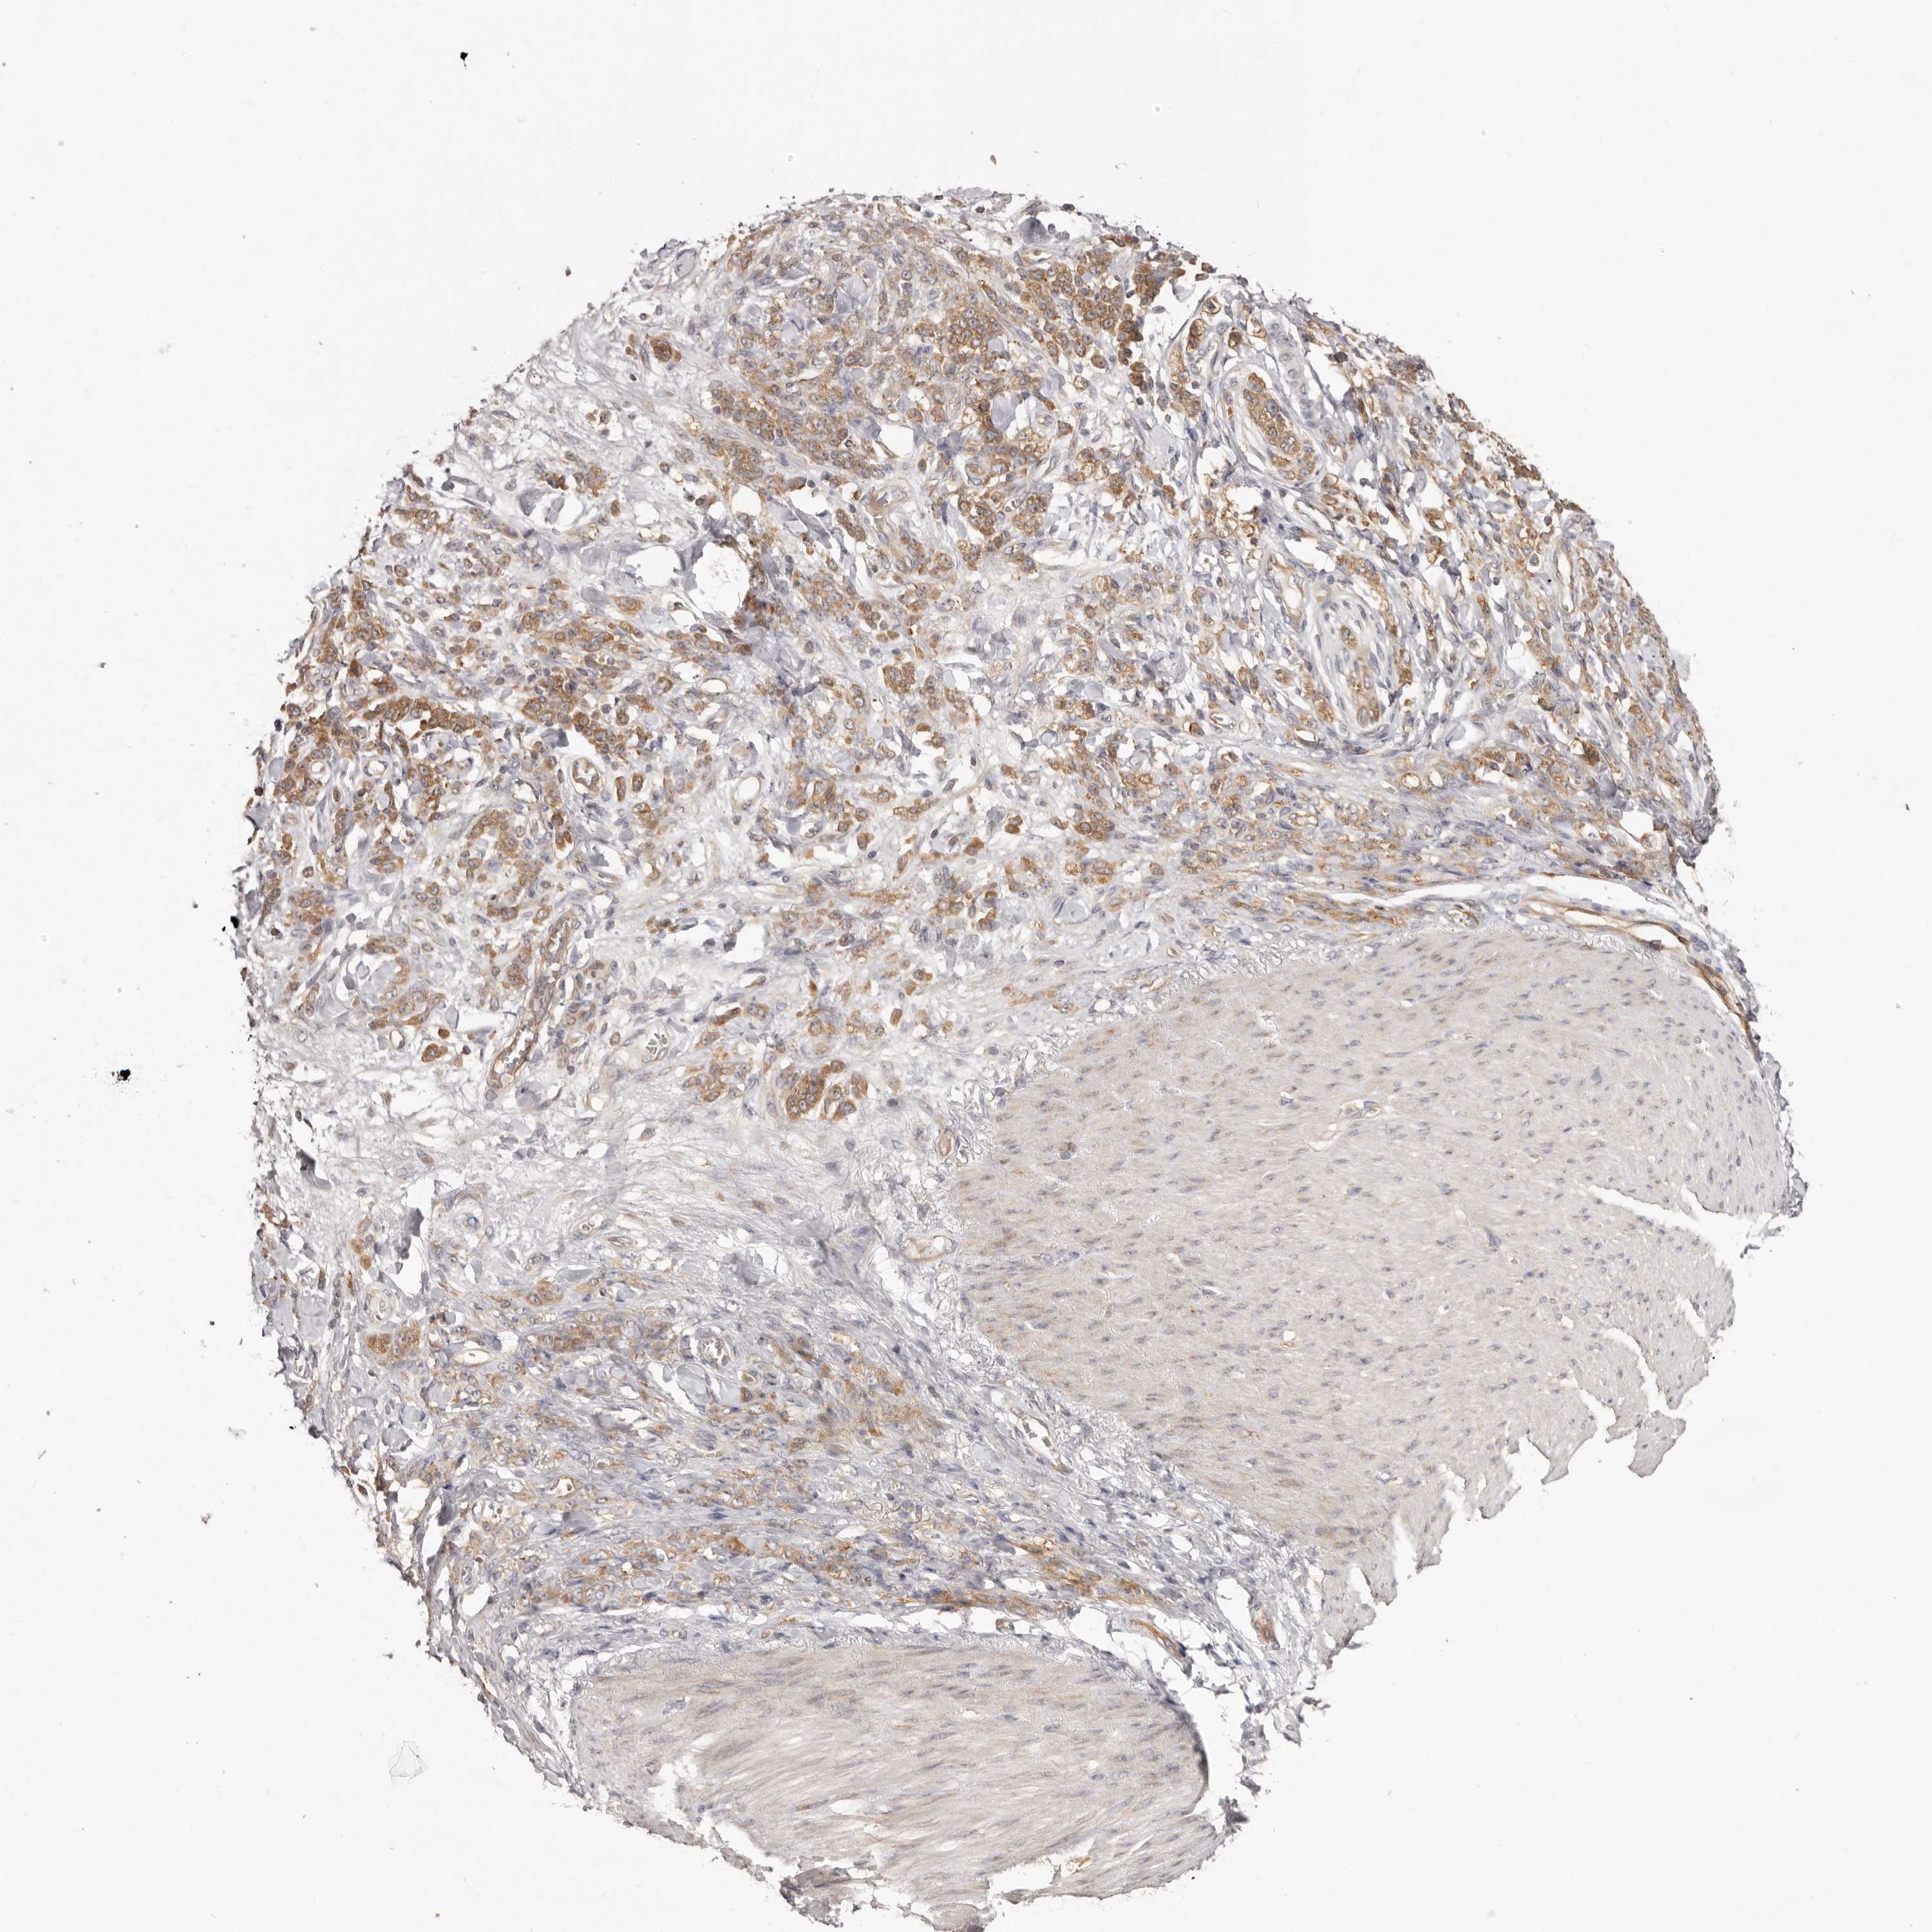

STOMACH CANCER - Protein expressioni

A mouse-over function shows sample information and annotation data. Click on an image to view it in a full screen mode. Samples can be filtered based on level of antibody staining by selecting one or several of the following categories: high, medium, low and not detected. The assay and annotation is described here.

Note that samples used for immunohistochemistry by the Human Protein Atlas do not correspond to samples in the TCGA dataset.

Antibody stainingi

Antibody staining in the annotated cell types in the current human tissue is reported as not detected, low, medium, or high, based on conventional immunohistochemistry profiling in selected tissues. This score is based on the combination of the staining intensity and fraction of stained cells.

Each image is clickable and will lead to virtual microscopy that enables deeper exploration of all samples and also displays staining intensity scores, fraction scores and subcellular localization as well as patient and tissue information for each sample.

Antibody HPA027901

Staining

High

Medium

Low

Not detected

Intensity

Strong

Moderate

Weak

Negative

Quantity

>75%

75%-25%

<25%

None

Location

Nuclear

Cytoplasmic/membranous

Cytoplasmic/membranous,nuclear

Adenocarcinoma, NOS